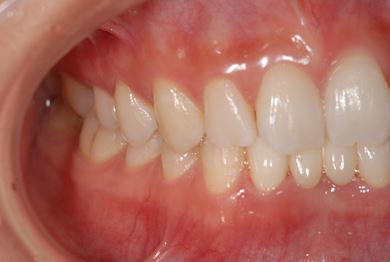

| 主訴 | 下前歯の色が気になるので、ホワイトニングかセラミック治療できれいにしたい。(下前歯2本は乳歯でした) | ||||||||||||||||||||||||||||||||

| 治療方針 | 下顎前歯、乳歯を抜歯し、セラミック治療にて審美的回復を行う。 | ||||||||||||||||||||||||||||||||

| 治療内容 | エンプレスジルコニアフレームオールセラミッククラウンブリッジ4本 | ||||||||||||||||||||||||||||||||

| 総治療費 | 723,450円 | ||||||||||||||||||||||||||||||||

| 治療期間 | 2ヶ月 |